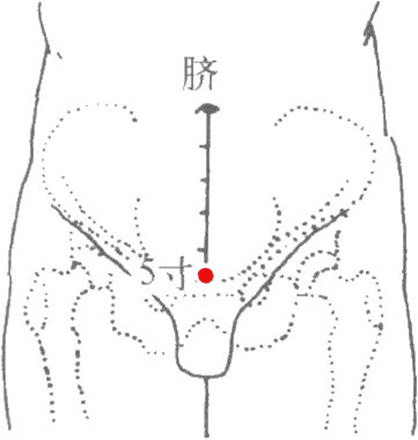

標準定位:曲骨穴在下腹部,當前正中線上,恥骨聯合上緣的中點處[6]。

曲骨穴位於腹正中線,臍下5寸,恥骨聯合上緣上方凹陷處[6]。

曲骨穴位於下腹部,當前正中線上,恥骨聯合上緣。仰臥取穴[6]。

曲骨穴在下腹部的位置

曲骨穴在下腹部的位置